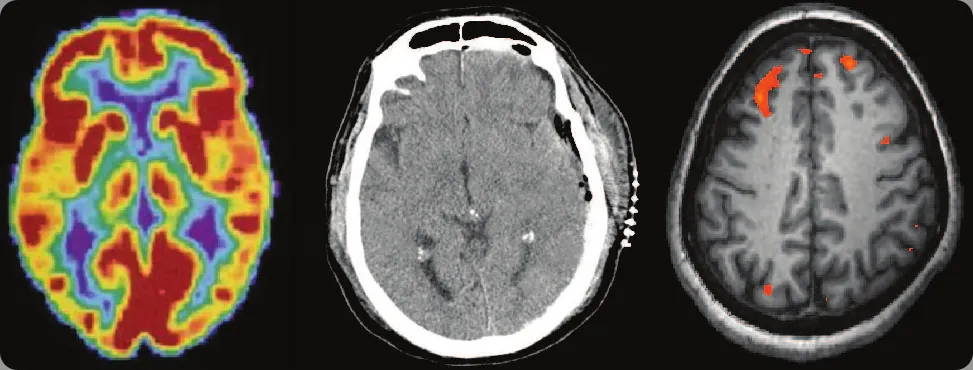

Ilustracja 3.1 W zależności od wyboru technik obrazowania otrzymujemy różne informacje na temat funkcjonowania mózgu. Od lewej: obraz uzyskany metodą pozytonowej tomografii emisyjnej (PET), tomografii komputerowej (TK) i czynnościowego rezonansu magnetycznego (fMRI). (Źródło: obraz po lewej: modyfikacja za amerykańskim Departamentem Zdrowia i Usług Społecznych, Narodowy Instytut Zdrowia (National Institutes of Health, NIH); obraz środkowy: modyfikacja za „Aceofhearts1968”, Wikimedia Commons; obraz po prawej: modyfikacja pracy Kim J., Matthews N. L., Park S.).